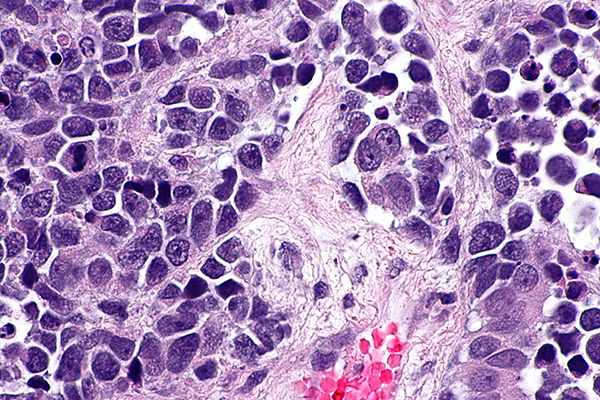

Another component in the management of cancer patients involves the grading of cancers which describe the appearance of cancer cells. It refers to how cancer cells look to a pathologist while examining the cells under a microscope. They can be classified into low or high-grade cancers.

Low grade cancers have abnormal cells that look a lot like normal cells under the microscope.

These cells and tumors grow slowly and are well differentiated cancers.

High grade cancers do not resemble what a normal cell looks like. These abnormal looking cells tend to grow rapidly and are more likely to spread to lymph nodes and different areas of the body. High grade cancers are poorly differentiated cancers.